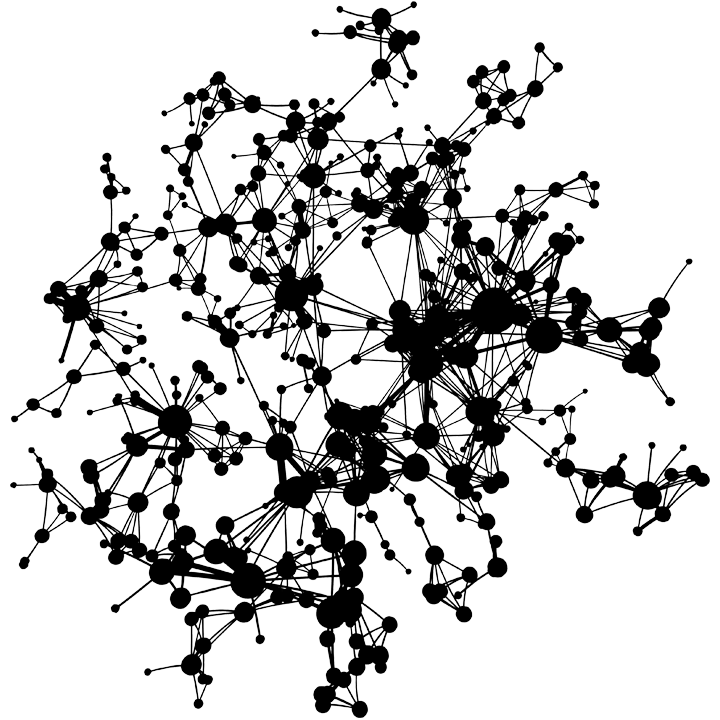

Diseasome Network

The Diseasome Network is a network of diseases based on the similarity in genetic mutations causing them, derived by Vidal et al.